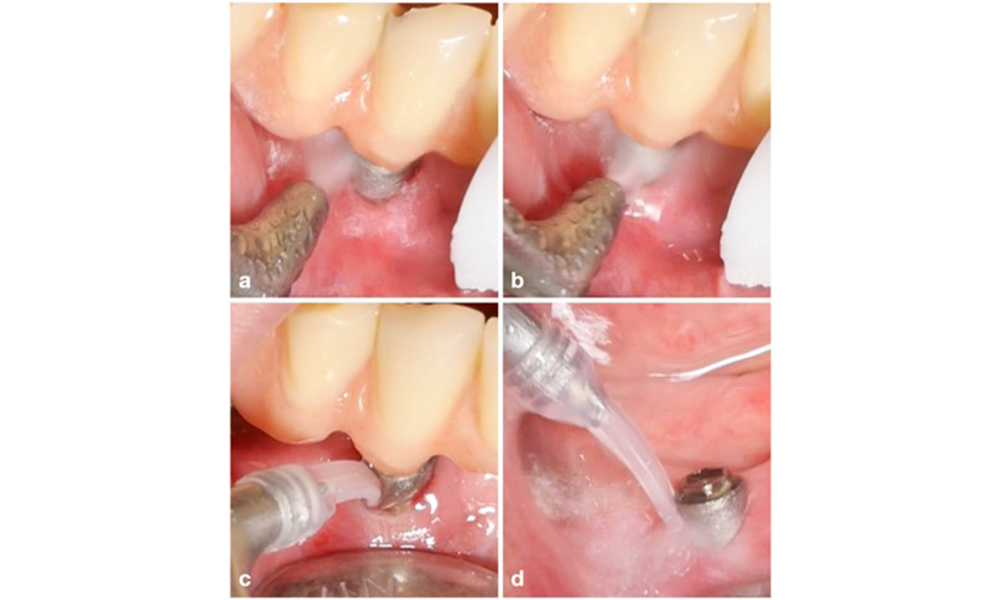

Le choix de l'équipement dépend des circonstances cliniques, comme la distinction entre le tartre et la plaque molle. Ainsi, en cas de tartre, il convient d'utiliser d'abord des curettes en titane ou en plastique, ou des embouts spécialement conçus pour les détartreurs à ultrasons, puis un appareil d'aéropolissage (figure 7). Dans les cas où il n'y a qu'une accumulation de plaque molle, un dispositif d'aéropolissage peut suffire. Les dispositifs d'aéropolissage sont faciles à utiliser pour l'opérateur et le patient et sont au moins aussi efficaces que les instruments standard (Schwarz et al. 2015a).

La prise en charge de la péri-implantite sur les implants jugés traitables consiste en une phase non chirurgicale, qui est souvent suivie d'une intervention chirurgicale. Pour l'approche non chirurgicale, des mesures similaires à celles appliquées pour le traitement de la mucosite péri-implantaire sont utilisées ; sur la base d'expériences de laboratoire, les dispositifs d'aéropolissage avec une buse sous-gingivale semblent offrir certains avantages en termes d'élimination du biofilm, par rapport aux instruments manuels ou à ultrasons (Herrera et al. 2023 ; Moharrami et al. 2019 ; Ronay et al. 2017) (figure 9).